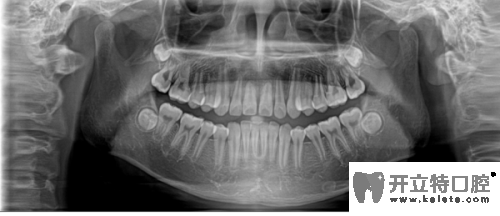

牙齒全景片

合肥崔勁松口腔正畸醫(yī)生說,矯正前做檢查是對(duì)顧客的牙齒和口腔健康負(fù)責(zé)。在做CT/全景片是能清楚的檢查到牙槽骨是否健康、有沒有牙周炎、阻生齒等情況,所以矯正治療前檢查是特別重要的。

其實(shí),正畸前的全景片檢查也是為了能更好的了解口腔情況,例如牙齒囊腫、牙根被吸收、腫瘤等,如果正畸醫(yī)生不拍這個(gè)片子,在做矯正之前就不會(huì)發(fā)現(xiàn)這些情況,那就是屬于很不負(fù)責(zé)的做法。全景片還可以的測(cè)定牙齒傾斜角度、牙根情況、牙槽骨質(zhì)情況、牙周軟組織情況,解剖牙齒形態(tài)的測(cè)量,能讓醫(yī)生在矯正前依靠全景圖像更精準(zhǔn)的分析、設(shè)計(jì)治療方案。